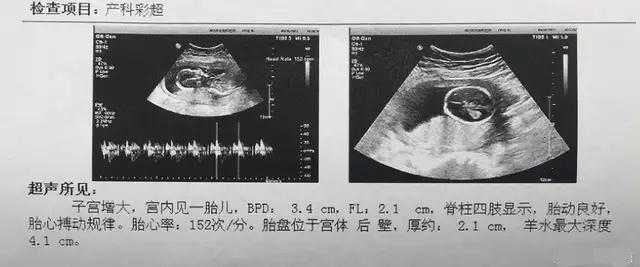

双顶径、股骨长、腹围、头围、胎心率、羊水、胎盘、胎位、脐带、脊柱、胎动等检查。